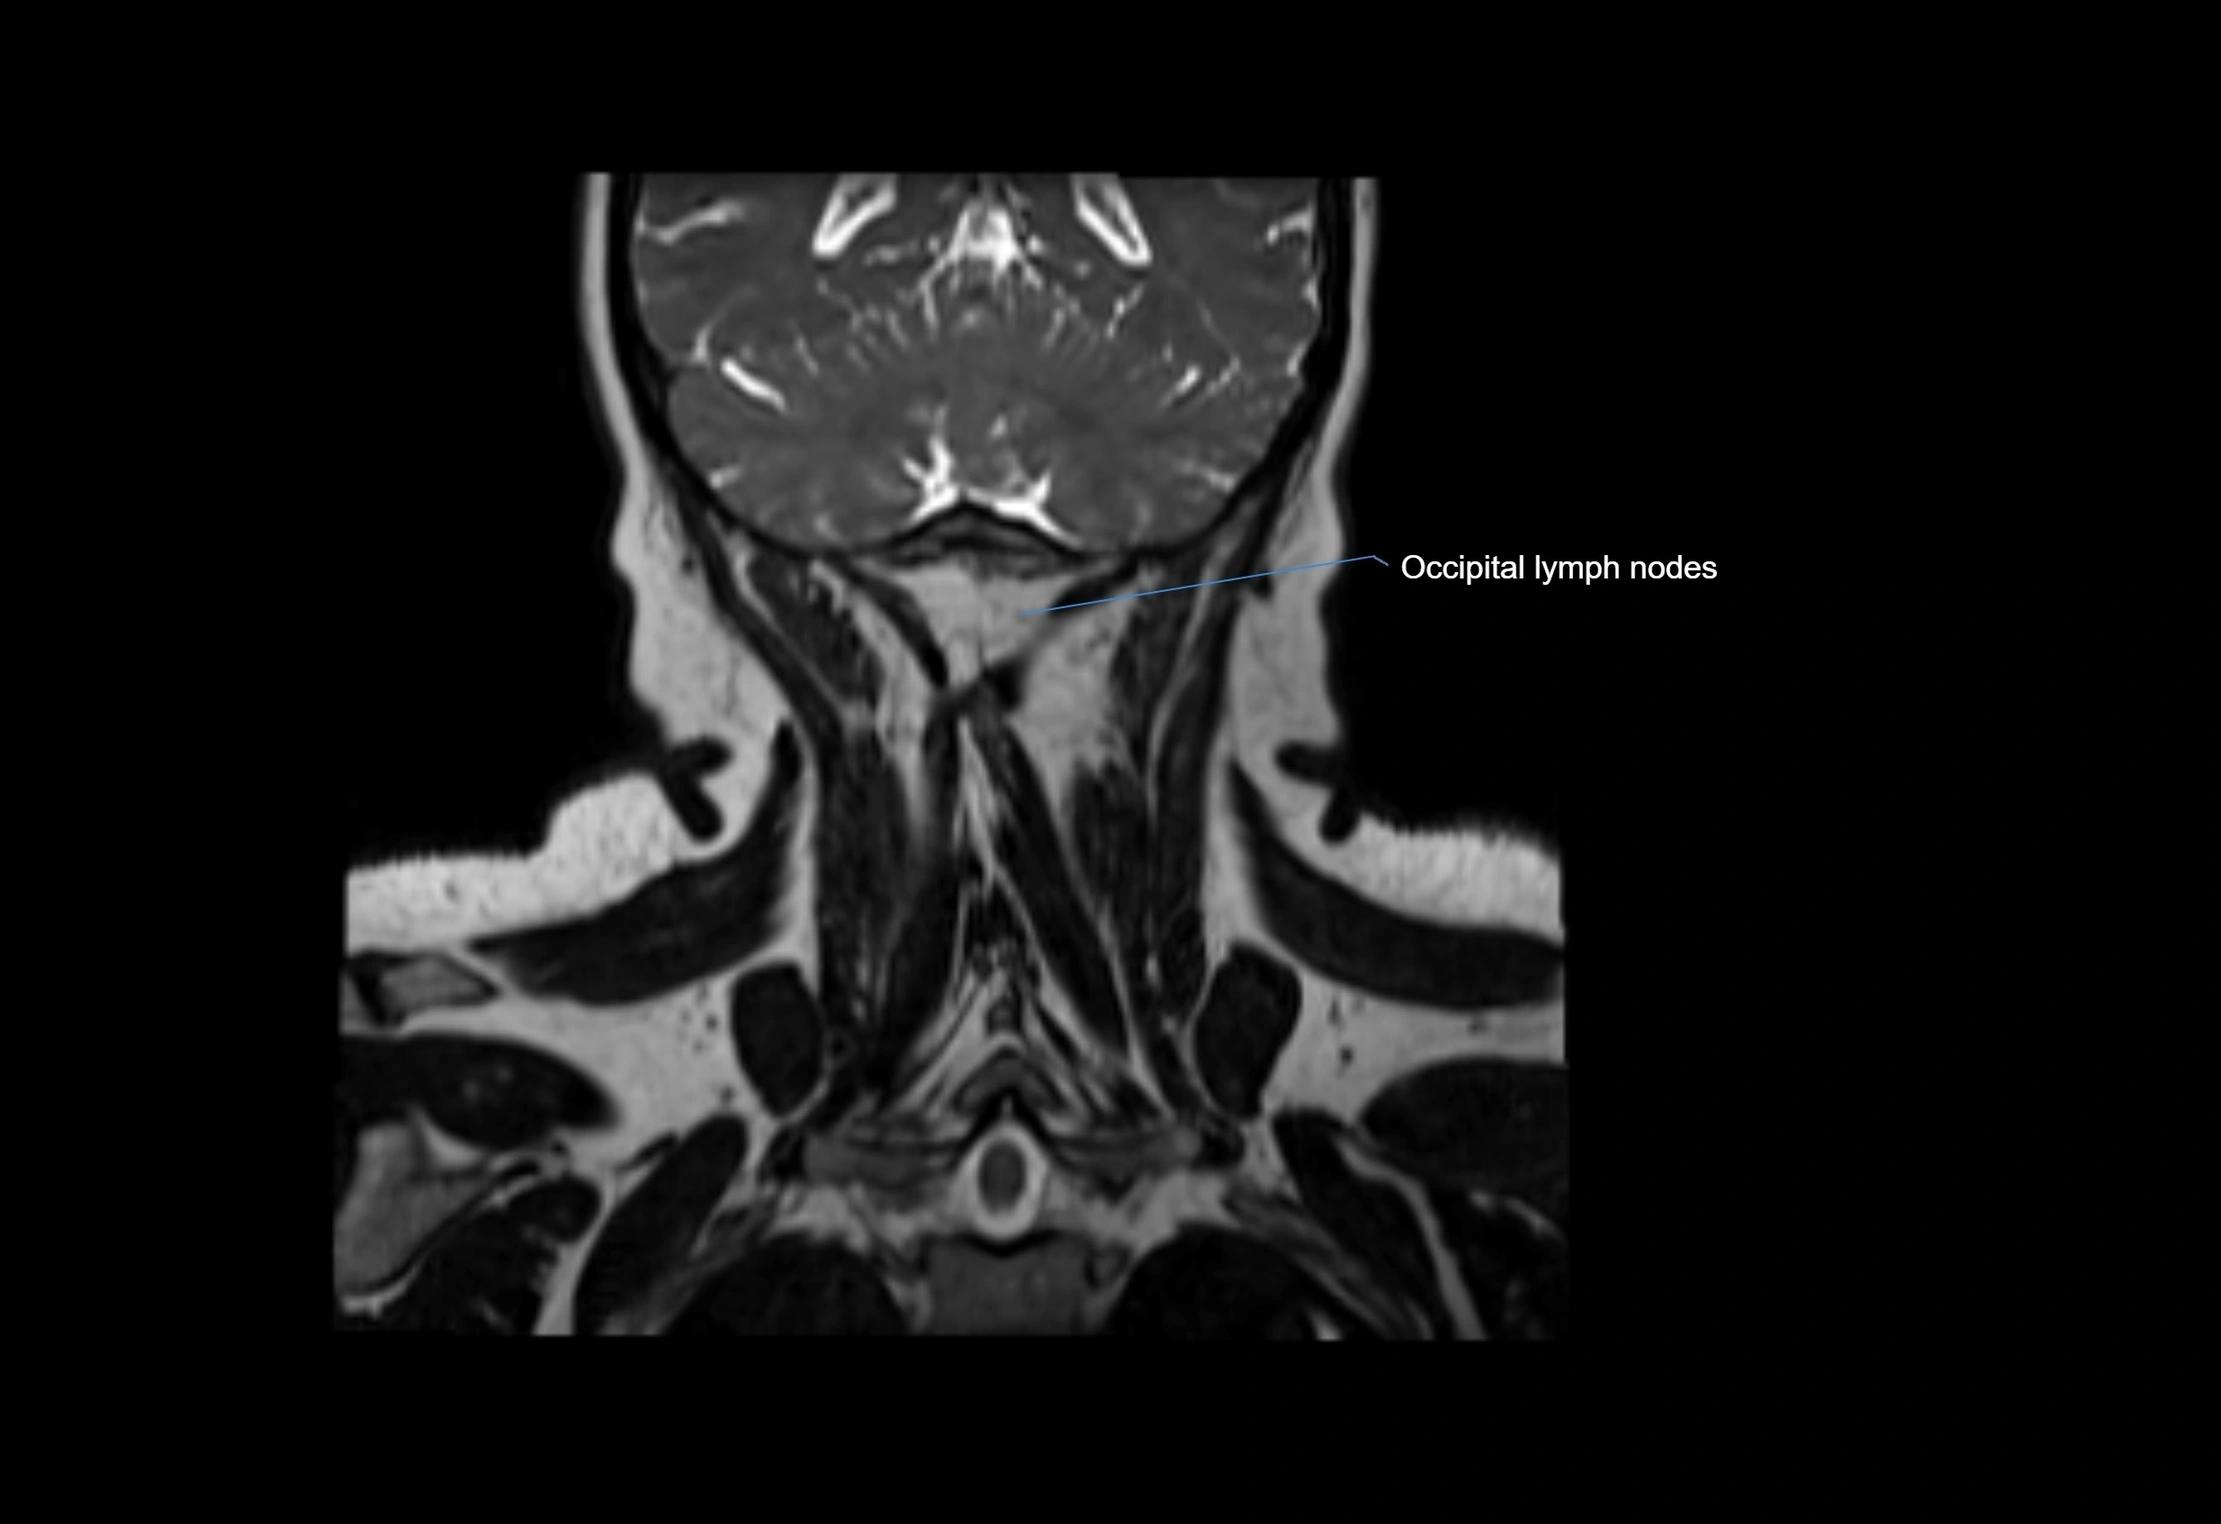

Accessory lymph nodes

Accessory lymph nodes are small, secondary lymph nodes located along the main facial and cervical lymphatic chains, often adjacent to primary lymph nodes, such as preauricular, submandibular, or occipital nodes. They are typically less than 5 mm in diameter, embedded within subcutaneous fat or connective tissue, and may be variable in number and location. These nodes provide additional filtration and immune surveillance for lymph collected from the face, scalp, and neck regions. Accessory lymph nodes are usually non-palpable in healthy individuals but may enlarge in response to infection, inflammation, or metastasis, making them clinically significant.

• Found along primary lymph node chains, including preauricular, submandibular, parotid, and occipital regions

MRI images

image